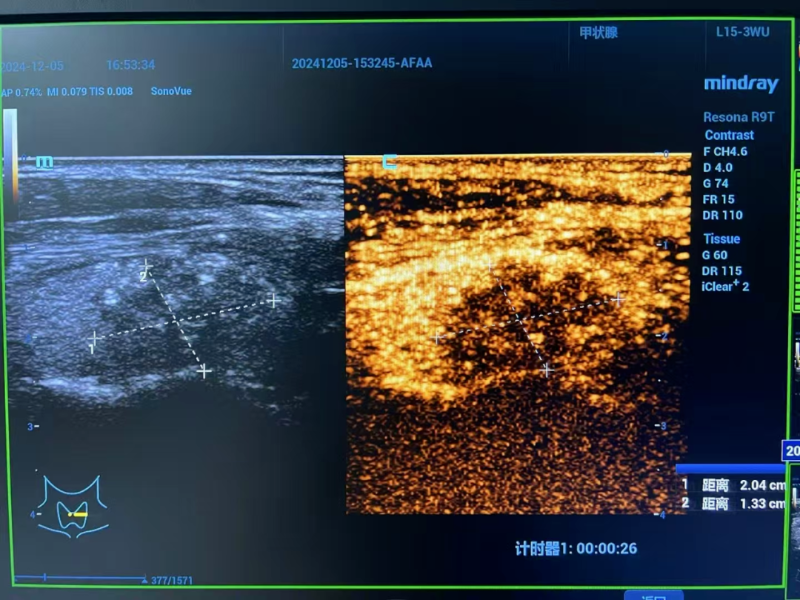

△術后評估

術后超聲造影檢查喜傳捷報:消融區域嚴密包繞癌灶,癌細胞無處遁形。李女士嗓音清晰如初,頸部痛感幾近于無,僅留微小創口,外觀幾無影響,身心恢復情況良好,術后次日即達出院標準,順利回歸生活正軌。